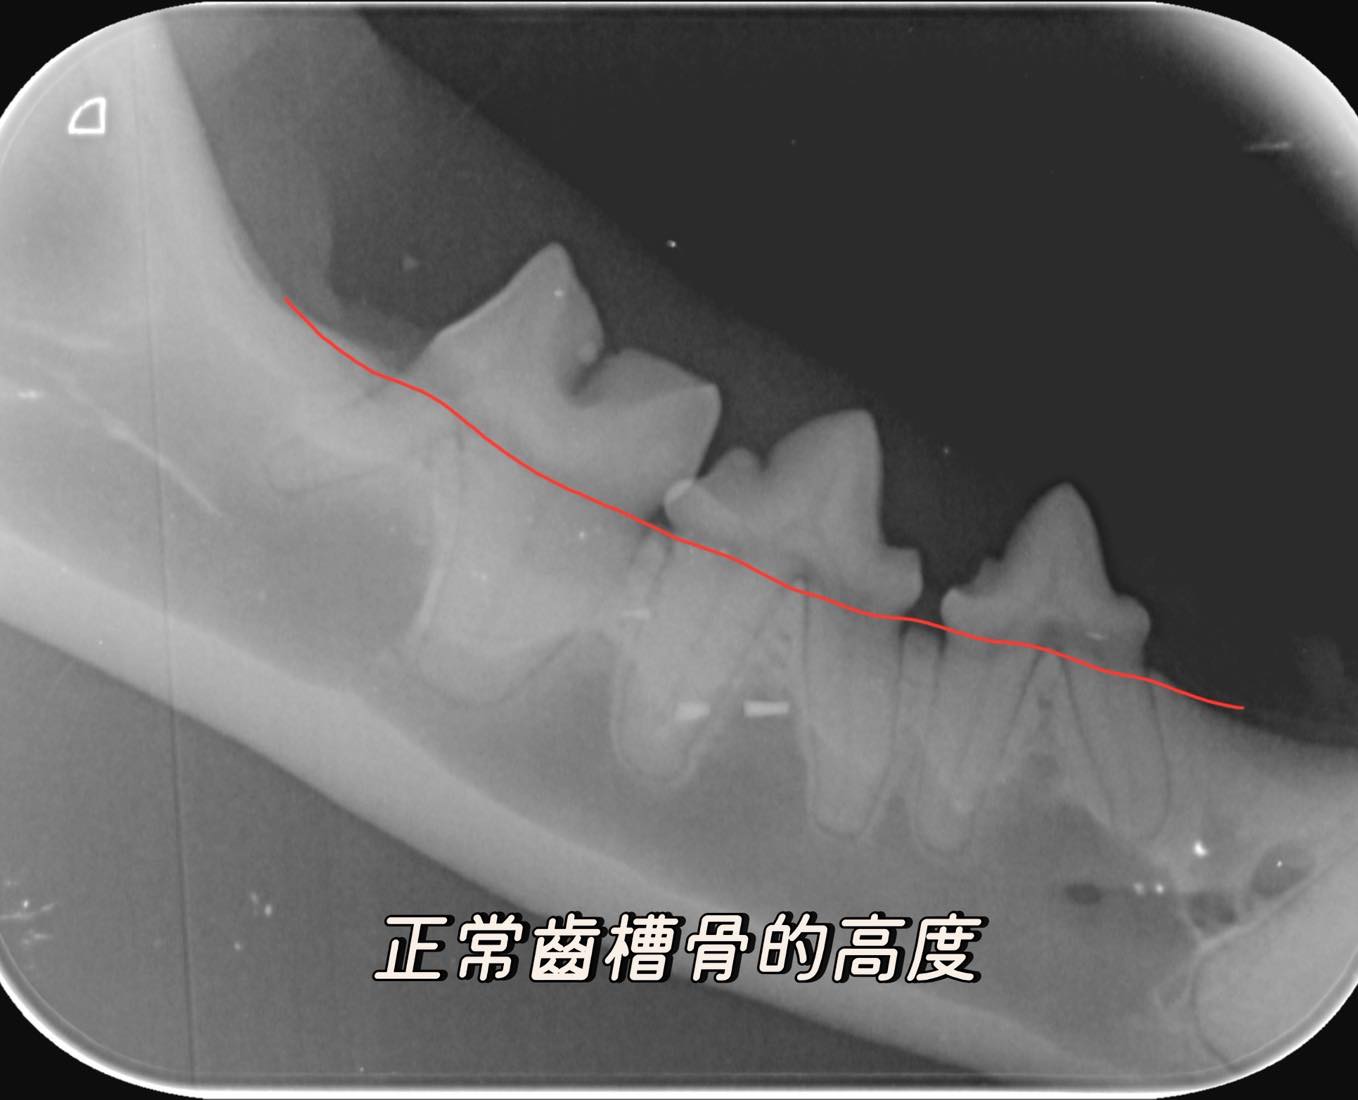

• 全口X光攝影 初步的牙周狀況,我們大概在前幾個階段有個基本的了解,但如果要知道牙根、根尖、牙髓腔、齒槽骨的狀況,我們還得需要讓動物們在麻醉的狀況下,嘴裡放入牙科X光片來拍攝記錄不同部位影像,狗狗一般總共會拍攝16-18張,貓咪則是8-10張。

1. 發現隱藏的疾病 動物的牙齒表面可能看起來健康,但X光下卻看到膿瘍、齒槽骨流失、牙齒斷裂、阻生齒或齒吸收病變。避免錯誤診斷,進而導致動物必須在短時間內,再次被麻醉處理上一次本就該被治療的牙齒疾病。

3. 評估牙根與顎骨健康 許多牙科疾病影響牙根及周圍的骨骼,如牙周病。X光能評估完整牙周狀況,判斷牙齒是否可以保留,或是否有更深層的感染需要治療。